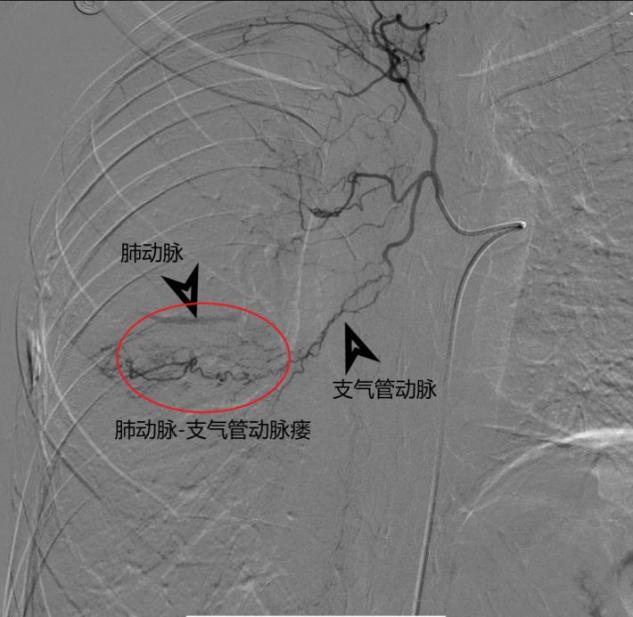

近日,在介入与血管外科张喜成主任医师指导下,程龙副主任医师及顾铖涛医师在DSA下造影找到了病变出血的原因——原来患者存在肋间动脉、支气管动脉肺动脉瘘。于是决定为患者行选择性动脉栓塞术。术中,如下图所示,医生用头发丝样的微导管超选择供血血管,尽可能避开对正常血管的影响后,用栓塞微球将瘘口堵塞住进行精准栓塞,整个手术约1个小时,术后复查咯血症状消失。在医护人员的精心照料下,术后10天,患者顺利康复出院。